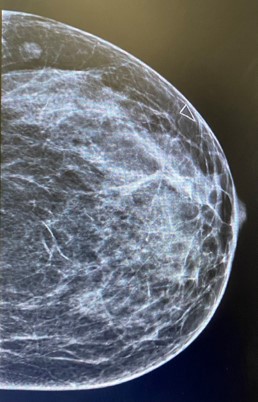

Left breast and axilla ultrasound and Mammogram showed: Left breast palpable lesion with architectural distortion in the upper lateral mid/anterior third at 3:00, It measures 0.9 cm and seen with no significant vascularity. A clip was placed.

Figure 1: Left mammographic views ML of the left breast showing an irregular, spiculated, high-density mass in the upper outer quadrant. The lesion causes architectural distortion without associated calcifications. Findings are consistent with desmoid-type fibromatosis confirmed on histology.

Mammography presents irregular walled and highly dense lesion with no calcifications mimicking sometimes breast carcinoma [6].

Radiologic evaluation of our case revealed soft tissue mass inducing architectural distortion.